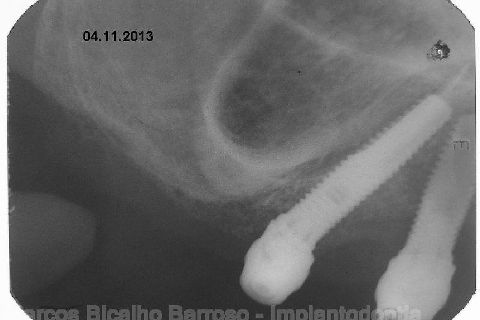

Atualização do caso clínico que já postei, "REABILITAÇÃO EM MAXILA ATRÓFICA COM IMPLANTES", um caso que inclui expansão do rebordo estreito com cinzel e martelo, expansores rosqueáveis, enxerto e instalação dos implantes distais inclinados tangenciando seio maxilar. Inclui esvaziamento do forame nasopalatino e preenchimento com biomaterial para instalação de dois implantes próximos dele. Cirurgia realizada em única sessão, com instalação dos 6 implantes. Para os colegas que não conheceram e/ou esqueceram da apresentação, este é o resumo do caso na fase cirúrgica.http://www.youtube.com/watch?v=BtvexFexRPA&hd=1